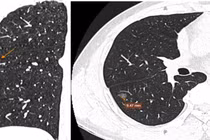

Lập tức, các bác sĩ đã tiến hành tiêm cầm máu cho bệnh nhân, hỗ trợ thở oxy để hồi sức và thực hiện các chỉ định cận lâm sàng khẩn. Qua phim chụp MSCT scan ngực cho thấy hình ảnh tổn thương bóng mờ phân thùy B1-2 phổi trái, nghi ngờ lao phổi bội nhiễm và dãn, tăng sinh động mạch phế quản hai bên kèm có tụ dịch nhầy trong lòng phế quản gốc và các phế quản thùy dưới phổi phải. Đồng thời kết quả xét nghiệm máu cũng cho thấy bệnh nhân bị thiếu máu mức độ nặng.

Kết quả chụp X-quang phổi tại giường ghi nhận bệnh nhân có tổn thương ở 2 đỉnh phổi nhiều, thiếu máu nặng hơn nên các bác sĩ thống nhất phương án can thiệp mạch đồng thời truyền 1 đơn vị hồng cầu lắng, hồi sức nội khoa cho bệnh nhân.